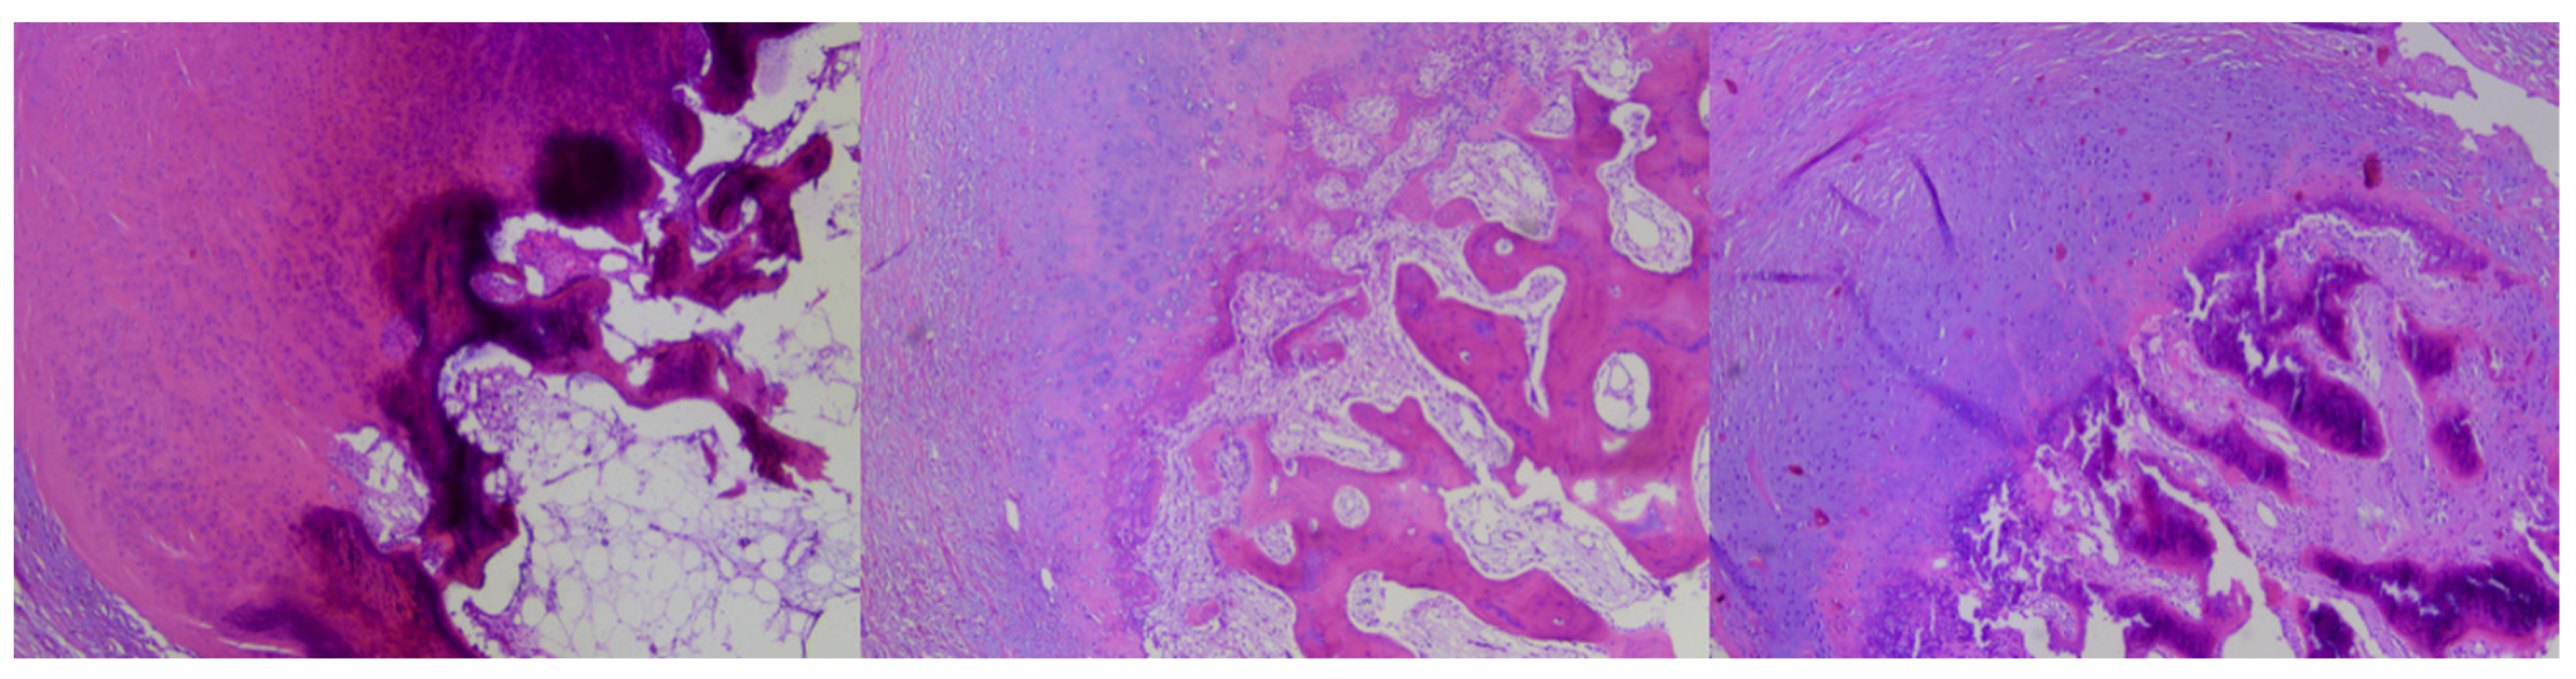

The sections were then transferred to Menzel (Thermo Scientific, Braunschweig, Germany) glass slides and stained with hematoxylin and eosin using the Leica ST5020 automatic stainer. After applying cover slips, the material was evaluated under a light microscope (Leica DM3000) by a specialist pathomorphologist with 8 years of experience in histological slide assessment (Figure 3).

Figure 3.

Three types of changes from the examined series: subungual osteochondroma (SO)—trabecular bone covered with hyaline cartilage (left), subungual exostosis (SE)—covered with fibrocartilage (right) and mixed type covered with hyaline-fibrocartilage (middle).